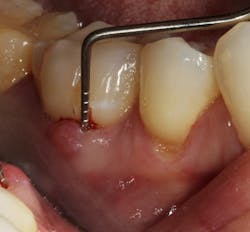

Figure 1: Molar with periodontal abscess due to furcation involvement

Figure 1a: Deep Class II furcation with an entrance smaller than the diameter of a curette tip

In other words, even experienced clinicians who access a root surface with flap surgery are sometimes limited in the amount of detoxification that can occur due to the depth of the defect and conventional instrumentation.11 Further limitations with mechanical access to defects can come in the form of furcations with multirooted teeth. The diameter of the entrance to root furcation is usually smaller than the average tip of a curette, which can make access difficult (figures 1 and 1a). Molars with bone loss that includes furcations are often downgraded in prognosis due to this access difficulty.12